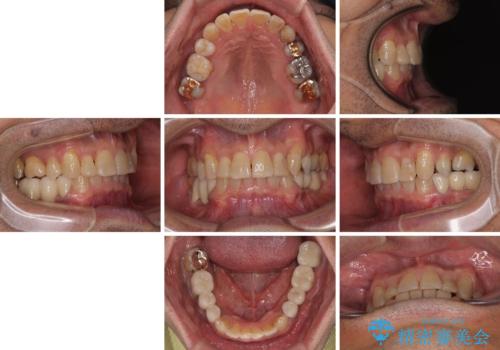

- 下顎両側の欠損と上顎前歯のデコボコを気にして来院された患者様です。

デコボコは今まで気にせずにいたそうですが、奥歯の欠損改善を機に、矯正治療に興味があるので、相談したいとのことでした。

奥歯に欠損が多く、矯正治療はやや難航することが予想されますが、患者様の希望もあり、上顎左右小臼歯を1本ずつ抜歯し、ワイヤー装置にて矯正治療を行うこととしました。

矯正歯科治療を行うに当たり、痛みや違和感を感じている歯の根管治療を行い、矯正治療中にインプラント埋入し、補綴治療と矯正治療を同時に終了できるように進めて行くこととしました。

銀歯やむし歯治療されている歯を抜歯する治療計画としたため、やや時間はかかりましたが、治療後の仕上がりには大変満足していただけました。